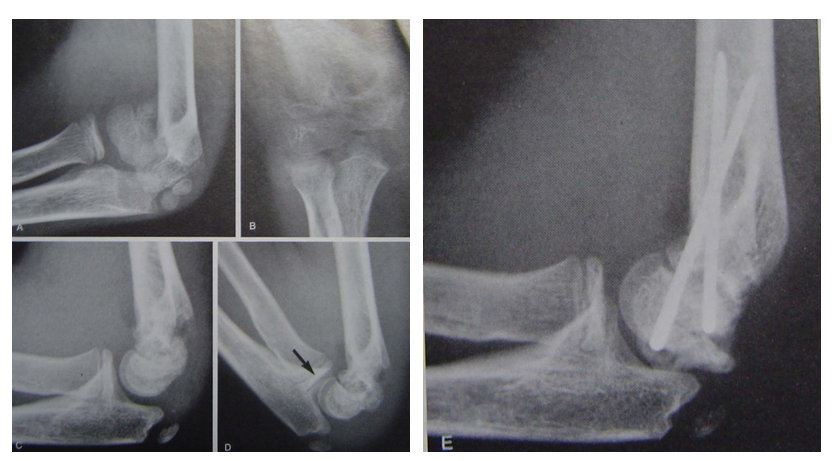

屈曲型伸直复位,伸直固定是方法之一。但石膏容易滑脱另一方法,伸直复位后屈曲肘关节,向后推挤维持复位,然后经皮克氏针固定。A、B术前x线片C 、D 手法复位 E 克氏针固定后